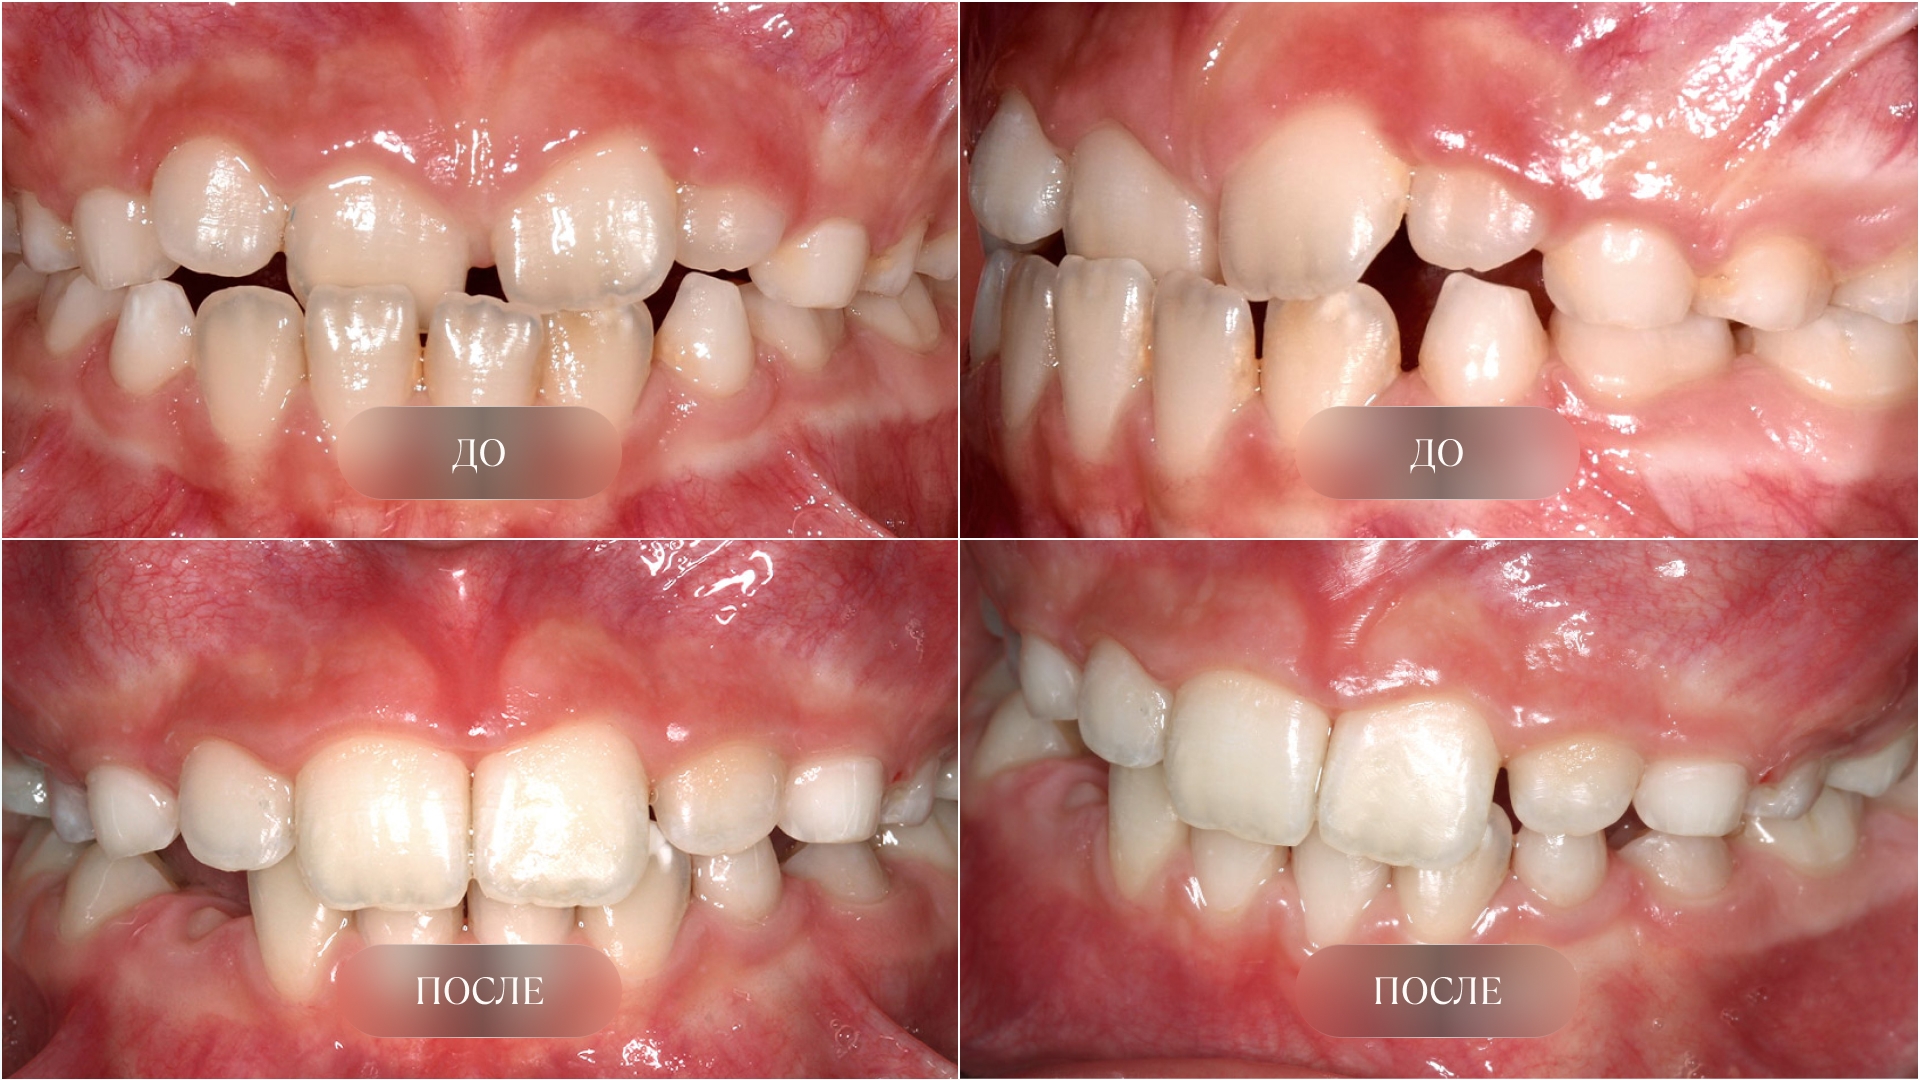

У детей мезиальный прикус составляет до 16% случаев. При данной патологии выражено переднее смещение нижней челюсти, нижние зубы перекрывают верхние. Нарушение заметно даже у маленьких детей. Если не вмешаться, оно усугубляется: меняются черты лица, процессы жевания затрудняются, может нарушаться работа височно-нижнечелюстных суставов, отвечающих за движения нижней челюсти.

Лечение мезиального прикуса у детей дает лучший результат именно в период активного роста. В это время врач может мягко направить развитие челюстей с помощью функциональных аппаратов, элайнеров или комплекса упражнений для мышц лица. Всё это может помочь избежать хирургического вмешательства в будущем. Чем раньше показать ребенка специалисту, тем быстрее удастся обнаружить проблему и приступить к коррекции, и тем меньше риск, что в будущем потребуется сложное лечение.

Мезиальный прикус у детей — это не просто «особенность» улыбки, а нарушение, при к�отором у ребенка нижняя челюсть выдвинута вперед и перекрывает верхние зубы. В норме верхние резцы слегка перекрывают нижние, обеспечивая таким образом условия для стабильного положения нижней челюсти и частично сдерживая её чрезмерный рост, который может возникать в случае отсутствия данного перекрытия. При мезиальном прикусе все наоборот: нижние зубы располагаются кпереди относительно верхних, а при выраженной деформации может происходить изменение черт лица.

Почему важно лечить мезиальный прикус в детстве

Многие родители надеются, что прогения со временем пройдет сама. Но этого не происходит — зубочелюстная система не формируется правильно без врачебной помощи. Напротив, с возрастом проблема усугубляется, лечение становится сложнее, дольше, дороже. Исправление мезиального прикуса у детей в период активного роста дает лучший результат и позволяет избежать тяжелых последствий.

Как исправить мезиальный прикус у ребенка: способы лечения

При мезиальном прикусе ортодонт работает в двух направлениях: сдерживает чрезмерный рост нижней челюсти и одновременно стимулирует развитие верхней.